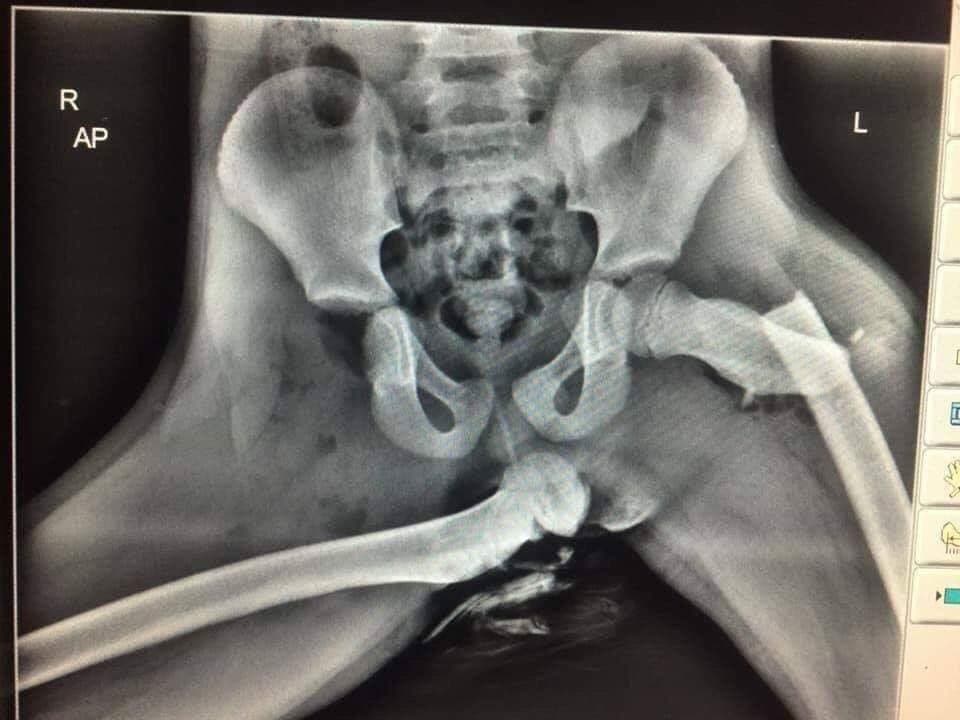

Une femme était assise sur le siège passager, les pieds sur le tableau de bord, lorsque la voiture dans laquelle elle était, est entrée en collision avec une autre. Le sergent Ian Price, résidant au Pays de Galles, a tenu à partager une image choquante dévoilant une radiographie des hanches de la victime. Il a partagé la photo sur Twitter afin d’engager une prise de conscience de la part des conducteurs et des passagers. Selon le sergent, la femme aurait subi une fracture de la hanche droite et une luxation de la hanche gauche suite à cet accident. Il déclare que sa vie a désormais changé pour toujours suite à ces faits. « Voici une radiographie des blessures horribles subies par le passager qui avait les pieds sur le tableau de bord au moment de la collision », peut-on lire sur la légende de l’image. « Si vous voyez votre passager le faire, arrêtez de conduire et montrez-lui ceci », ajouta-t-il.